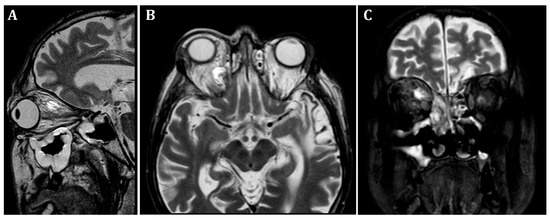

At the patient’s initial presentation at the Otolaryngology Department of the secondary hospital, the magnetic resonance imaging (MRI) of orbits revealed infiltration of the right frontal, ethmoid and maxillary sinuses, extension into the right orbit’s soft tissue and extraocular muscles with optic nerve invasion (Figure 1). The ophthalmological examination revealed central retinal artery occlusion. The treatment with ceftriaxone, vancomycin, fluconazole, mannitol and methylprednisolone was initiated. Due to clinical suspicion of mucormycosis, the patient was transferred to the University Hospital in Cracow.

Orbital MRI demonstrated a 23 × 15 × 14 mm abscess in the upper-medial quadrant of the right orbit, showing strong contrast enhancement and centrally elevated T2 signal. The lesion was adjacent to an area of infiltration, which also exhibited contrast enhancement and restricted diffusion. The process extended into the orbital adipose tissue, extraocular muscles and nasal cavity, causing osseous destruction of ethmoid cells, superior and middle nasal conchae, as well as the wall of the right maxillary sinus. The suspicion of erosion of the medial orbital wall (of the right orbit) was raised and later confirmed in CT imaging. Posteriorly, the infiltration progressed into the optic canal, involving the optic nerve, which appeared thickened and showed contrast enhancement. Additionally, a massive right maxillary sinus opacification and mucosal thickening were present.

Figure 1. Initial pre-operative magnetic resonance imaging. T2-weighted MRI scans of the orbits. (A)—sagittal, (B)—frontal, (C)—transverse planes. Visible infiltration of extraocular muscles and optic nerve. Inflammatory opacifications in ethmoid cells and maxillary sinus, extending into the orbital adipose tissue and extraocular muscles, causing osseous destruction of ethmoid cells.